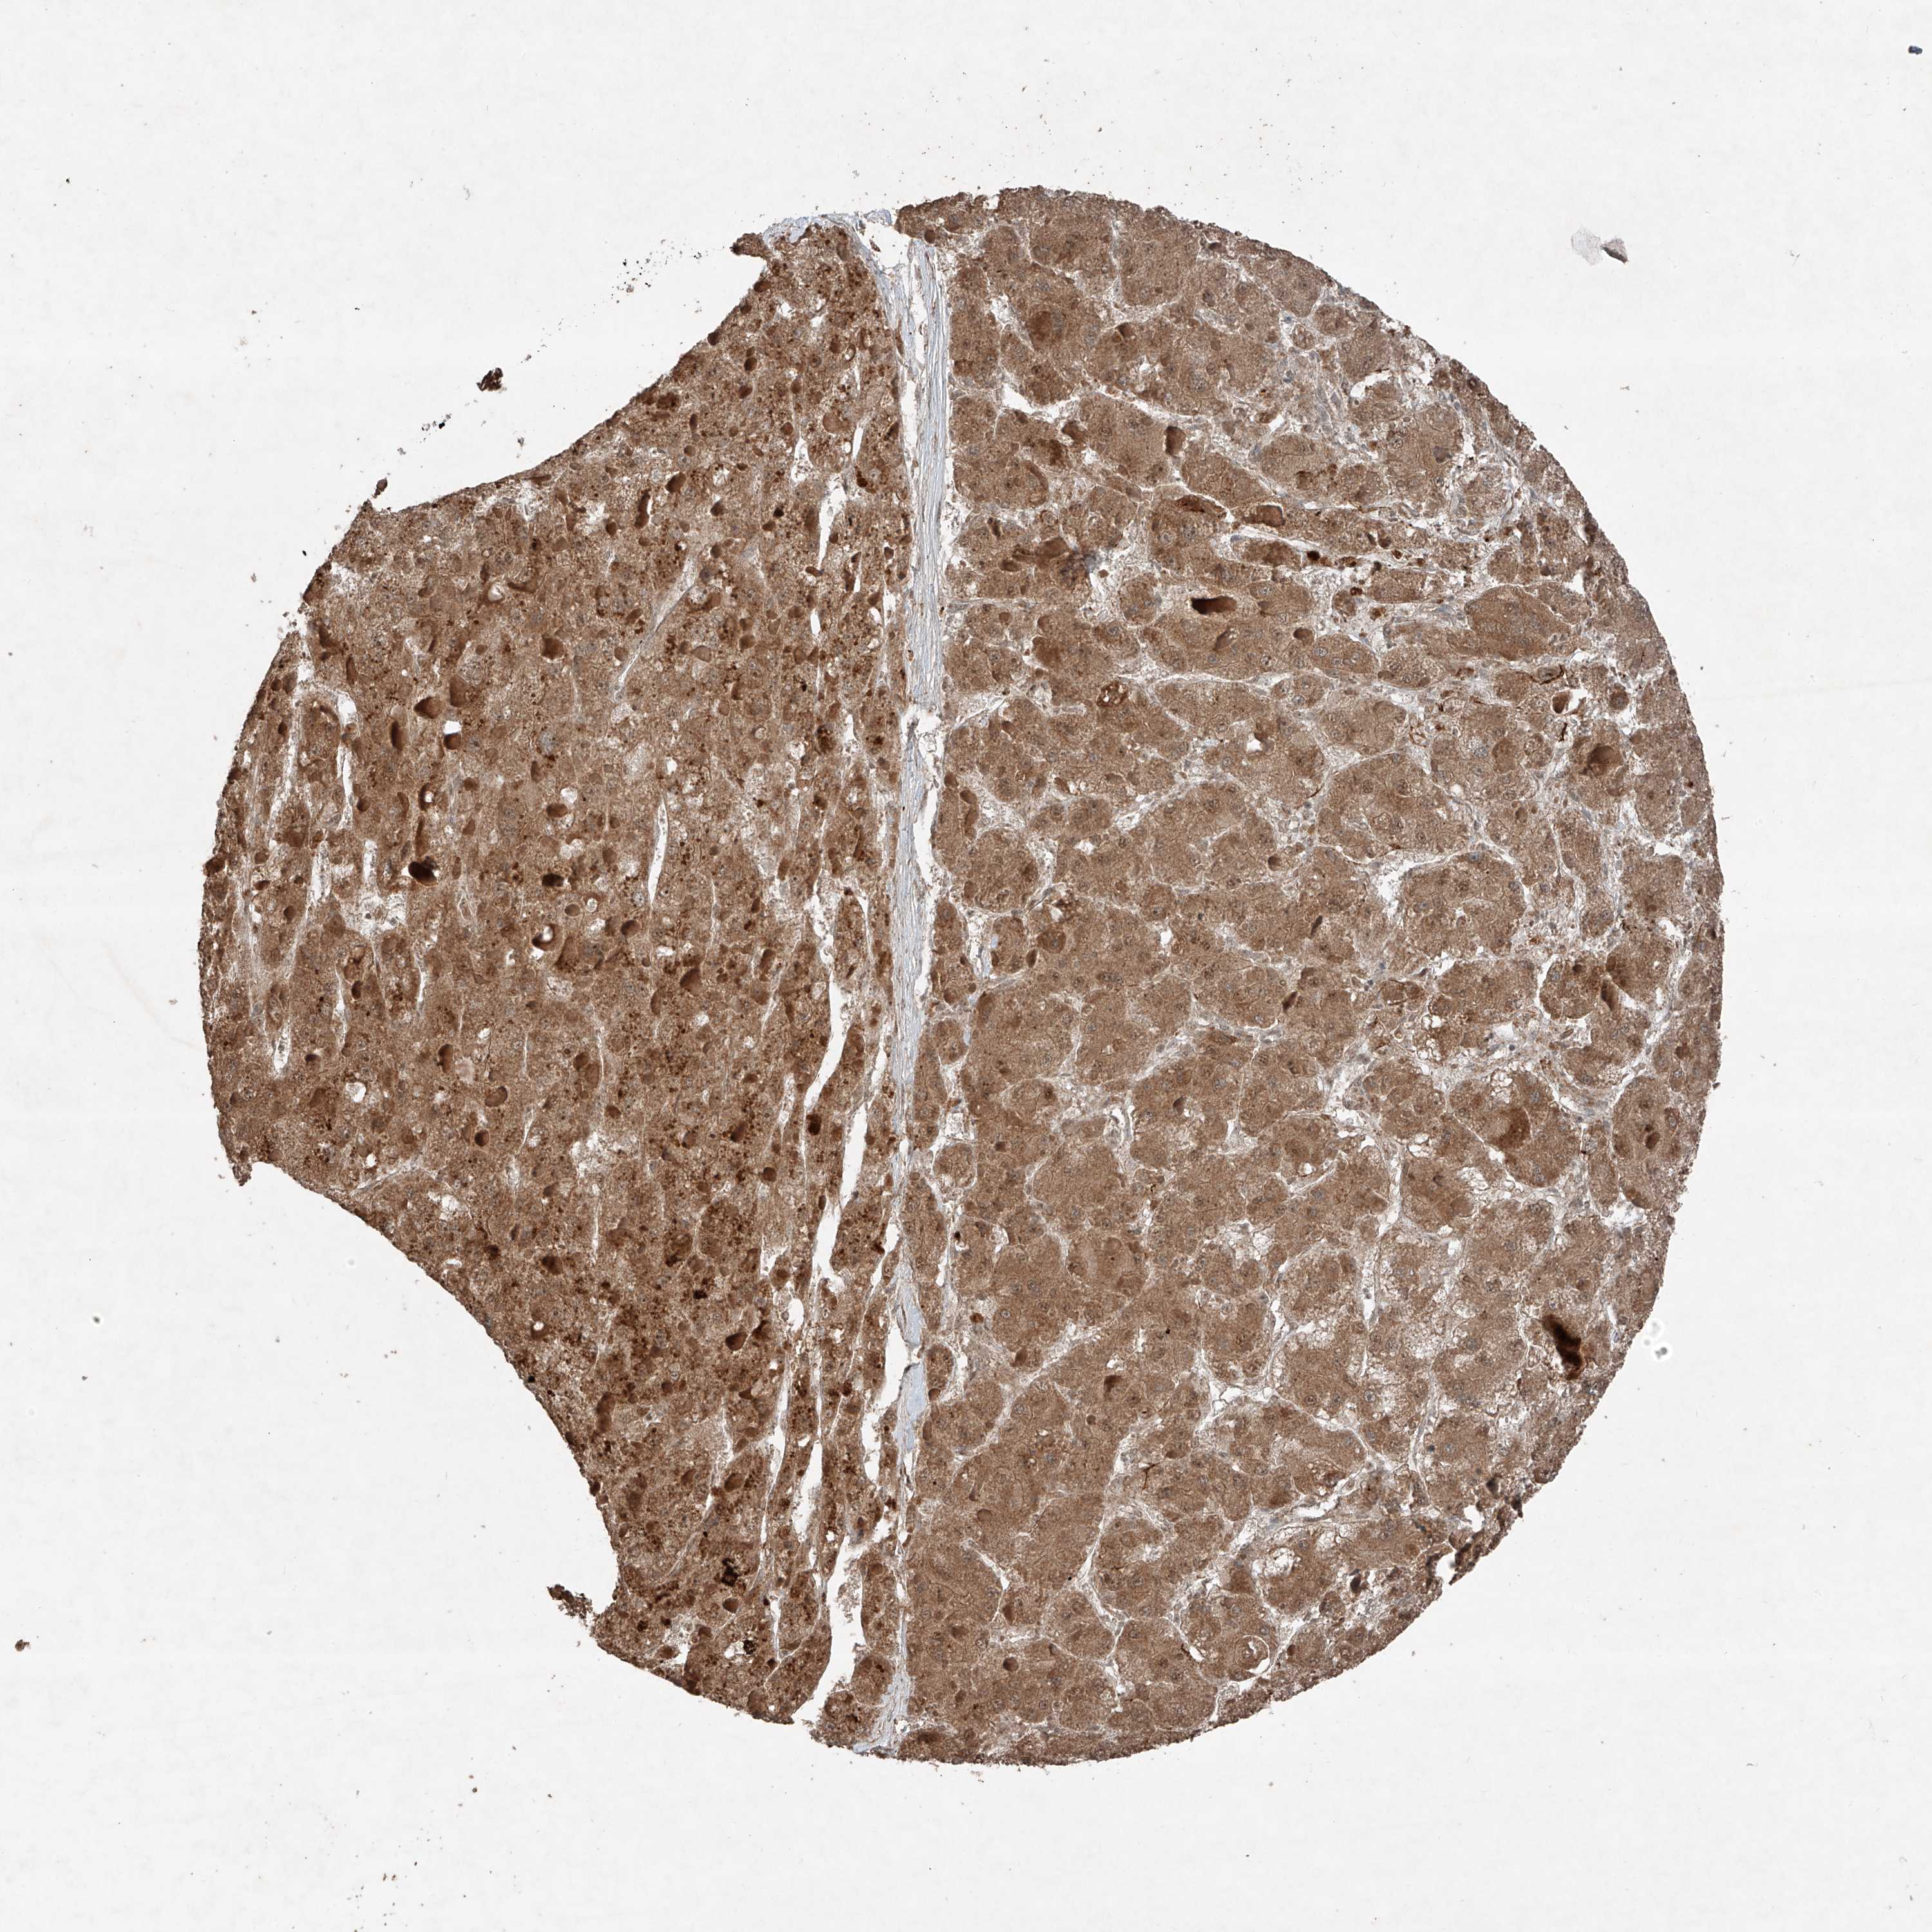

LIVER CANCER - Protein expressioni

A mouse-over function shows sample information and annotation data. Click on an image to view it in a full screen mode. Samples can be filtered based on level of antibody staining by selecting one or several of the following categories: high, medium, low and not detected. The assay and annotation is described here.

Note that samples used for immunohistochemistry by the Human Protein Atlas do not correspond to samples in the TCGA dataset.

Antibody stainingi

Antibody staining in the annotated cell types in the current human tissue is reported as not detected, low, medium, or high, based on conventional immunohistochemistry profiling in selected tissues. This score is based on the combination of the staining intensity and fraction of stained cells.

Each image is clickable and will lead to virtual microscopy that enables deeper exploration of all samples and also displays staining intensity scores, fraction scores and subcellular localization as well as patient and tissue information for each sample.

Antibody HPA031452

Staining

High

Medium

Low

Not detected

Intensity

Strong

Moderate

Weak

Negative

Quantity

>75%

75%-25%

<25%

None

Location

Nuclear

Cytoplasmic/membranous

Cytoplasmic/membranous,nuclear

Cholangiocarcinoma

Carcinoma, Hepatocellular, NOS